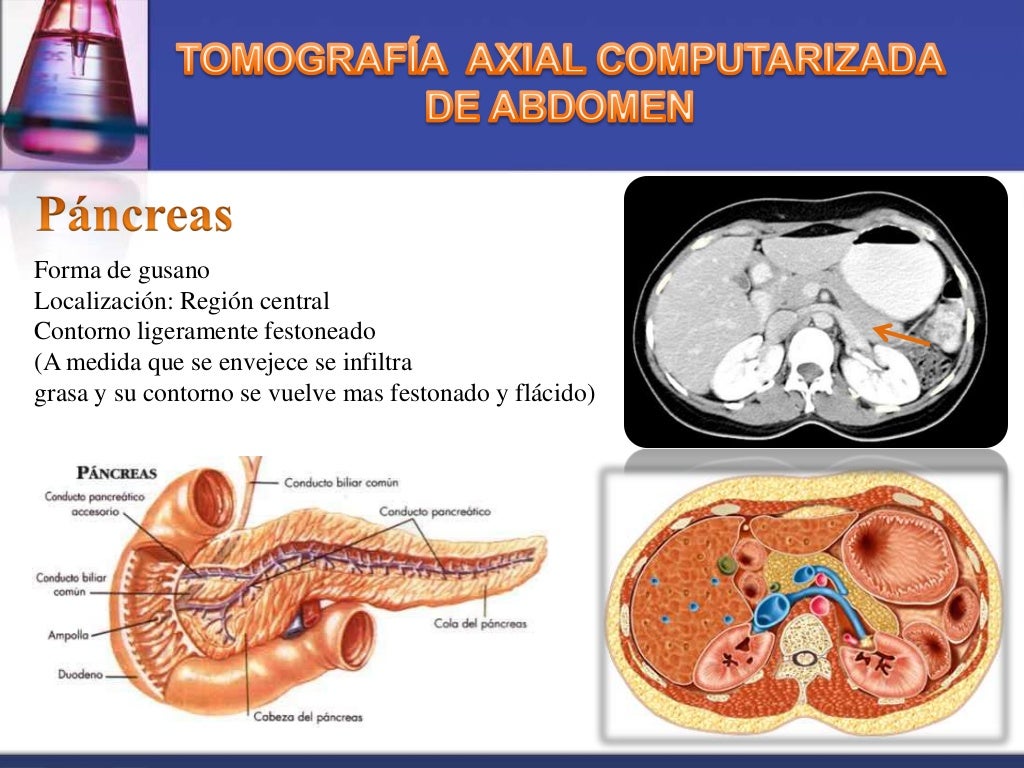

La tomografía computarizada, más comunmente conocida como exploración por tc o tac, es un examen médico de diagnóstico por imágenes.

que es una tomografia abdominal La tomografía computarizada, más comunmente conocida como exploración por tc o tac, es un examen médico de diagnóstico por imágenes. La angiotomografía computarizada del corazón es una forma útil de detectar arterias coronarias obstruidas. Una tomografía computada abdominal utiliza una máquina especial de rayos x para tomar imágenes del hígado, bazo, riñones, vejiga, estómago, intestinos, páncreas y glándulas. Una tomografía de abdomen es un estudio de imagen que ayuda a detectar problemas de salud en el área del abdomen. Una tomografía computada abdominal utiliza una máquina especial de rayos x para tomar imágenes del hígado, bazo, riñones,. La tomografía computarizada, tc, es un procedimiento con imágenes que usa equipo especial de rayos x para crear imágenes detalladas, o exploraciones, de regiones. Al igual que los rayos x. La angiotomografía computarizada podría costar menos que una.